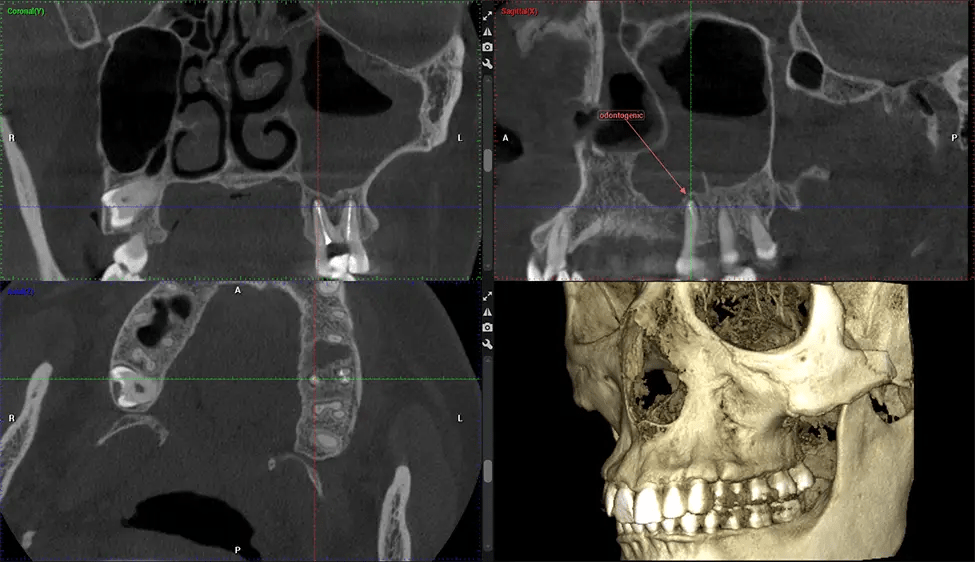

Cone Beam Computed Tomography (CBCT) is an advanced imaging technique used in dentistry and maxillofacial surgery to obtain detailed 3D images of the oral and maxillofacial structures. At Dr G Dental Studio, our CBCT scanners utilize a cone-shaped X-ray beam and a specialized detector to capture images from different angles. A computer then combines these images to create a 3D representation of the patient’s oral anatomy.

This 3D scan, called cone beam computed tomography, gives your dentist a more complete image of your oral anatomy and disease processes than a traditional X-ray. Unlike conventional X-rays, which capture a 2D image of your mouth from various angles, a 3D scan takes multiple digital X-rays for one image. It provides a complete view of your jaw, teeth, nerves, and soft tissues. This enhanced view allows dentists to detect minor issues not visible in traditional 2D scans, such as impacted wisdom teeth or bone fractures in the sinus cavity.

There are many benefits to using CBCT technology, especially compared to the traditional 2D X-ray format. One of the most significant advantages of CBCT scans is that they provide much more information than traditional X-rays. A scan lets your dentist see images from all angles of your jaw and mouth, including your sinuses, nasal cavity, cheekbones, and other surrounding areas. This added information helps your dentist craft a comprehensive treatment plan that addresses all aspects of your oral health.

Oral and Maxillofacial Surgeon Complex oral surgeries, orthognathic (jaw) surgery, and removal of impacted teeth. Offers precise, three-dimensional visualization of the skull, jaw, and craniocervical junction to enhance diagnostic accuracy and minimize surgical risks.

ENT Physician Diagnosing obstructive sleep apnea (OSA) and evaluating sinus and nasal cavity anatomy. Visualizes the entire pharyngeal airway to measure volume, pinpoint constrictions, and plan corrective surgery if needed.